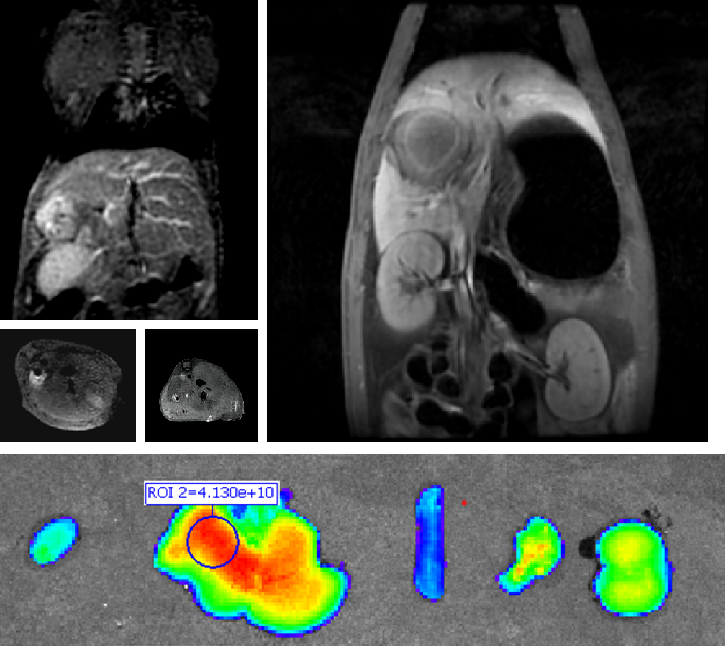

双模态造影剂PL002

普利制药自主研发的双模态造影剂PL002,已经获得美国FDA临床试验批件。PL002的研制首次提出通过整合磁共振技术,弥补现有荧光染料假阳性率高、透射深度有限等的短板,进而提升手术的精确性,降低手术过程中的风险,是全球首个获批临床试验的荧光/磁共振双模态造影剂。本项目预示着海南普利在造影剂领域的长期投入,并致力于开展独具特色的差异化国际化创新发展路径。